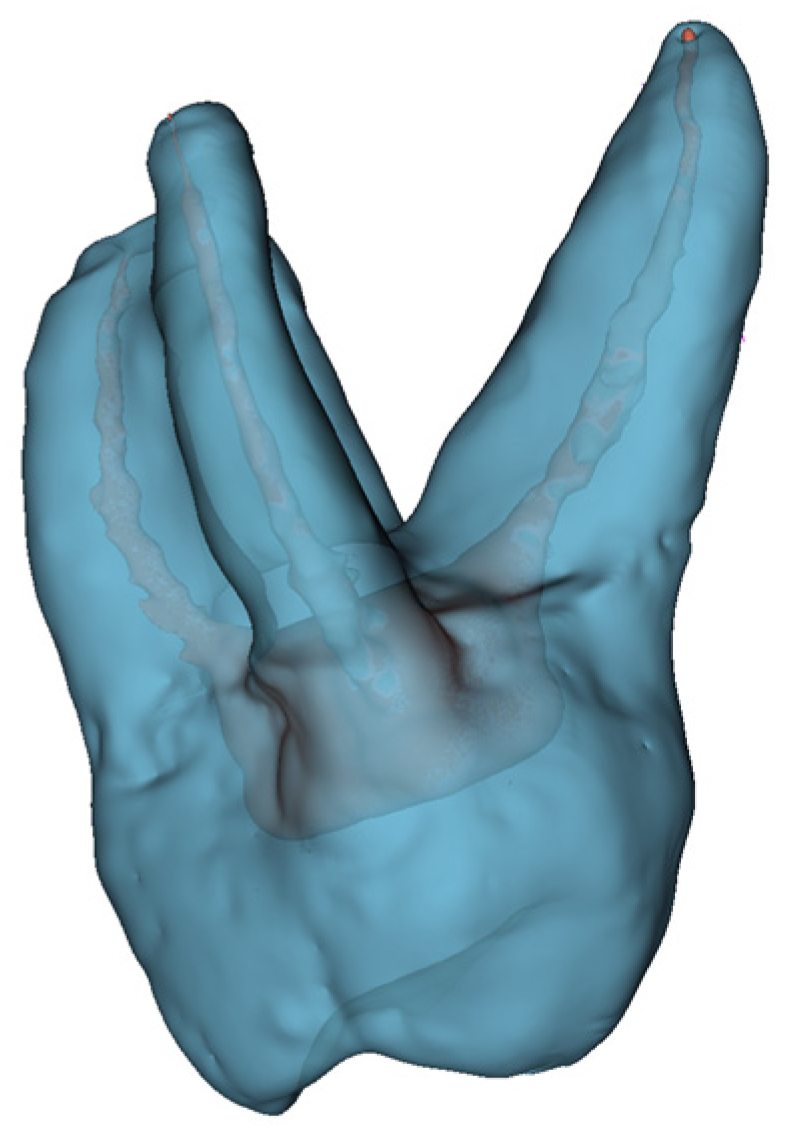

2.2. Mixed Reality-Based Solution

In this paper, we proposed an advanced computer system to support endodontic treatments, which is designed to run using MR goggles, i.e., the Microsoft HoloLens 2. It enables visualization of root canals and active interaction with them using eye movement and gestures. The system operates on the CT scan data, which were used to create 3D models. In the next step, the developed models were displayed on a Microsoft HoloLens 2 device to allow dentists to evaluate the root canals of the teeth. In Figure 3, the scheme of the development of the 3D model is shown, while Figure 4 presents the MR- based system to support endodontic treatments. The dentists have the option to rotate, scale, and move generated tooth models using HoloLens 2 standard gestures that are similar to the ones used in a real environment, to catch something and manipulate it. Users have almost real experience in using the application without the need for advanced and time-consuming training in using applications. The 3D models were developed and implemented in Autodesk Maya and exported to Unity. Finally, the 3D holograms are displayed in the Microsoft HoloLens 2 MR goggles. It turns out that the proposed approach allowed us to view more information at the same time than when using 2D pictures or 3D pictures. The 3D models displayed using Microsoft HoloLens 2 allowed users to see more and have a much better understanding of the complicated 3D structures.

Various types of software and hardware tools are required to develop and visualize holographic 3D models. In terms of hardware, the system is designed to run on Microsoft HoloLens 2. The structural models of teeth and root canals are reconstructed by a developed Python application and the models are exported into Unreal Engine (Epic Games, Potomac, MD, USA). To create the holographic 3D models of patients’ teeth, which are presented in Figure 5, DICOM RAW data from CT scans were used. By applying semi-automated algorithms, the CT scan is segmented. Every elementary volume component (i.e., voxels or Hounsfield units) of the CT scan is labeled manually and then processed. Here, the fill-between-slices algorithm was used. The application, which enables the creation of 3D holograms, was written in Python, see Figure 6. In the first step, a CT scan (DICOM data) was loaded. Next, each layer was reviewed to obtain the required range of minimal and maximal values for the entire CT scan. The values obtained are applied to select the appropriate range to obtain the best quality model. For example, the range of 0–50,000, where 0 denotes a black color and 50,000 white colors. The created range selection enables us to decide which pixels should be skipped in the generated model. It can be compared to printing black pictures on white paper. The printer is only placing black ink in black spots on white paper and skips everything where it should print in white color. Creating 3D models is the same situation. We decide which color values from the DICOM pictures should be used for creating the model and which are skipped as empty spaces.

In Figure 6, the model is created with values in the range of 2350–32,246, the selected pixels are marked red on an example preview of one CT layer. The values can be amended until the 3D model preview returns the best-quality model. Following that, we can run “cleaning” and smoothing algorithms. The final result is converted into OBJ format which is used to export the model to Microsoft HoloLens 2. To achieve the best quality and performance, a new HoloLens 2 project is created using the Unreal Engine application. Then, the Unreal new HoloLens 2 project obj file is configured with the created model. Next, we need to add appropriate lighting to view the model correctly and save the project at the end so it can be installed and run on a HoloLens 2 device.

Figure 5. The 3D holograms of the tooth, with visible root canals.